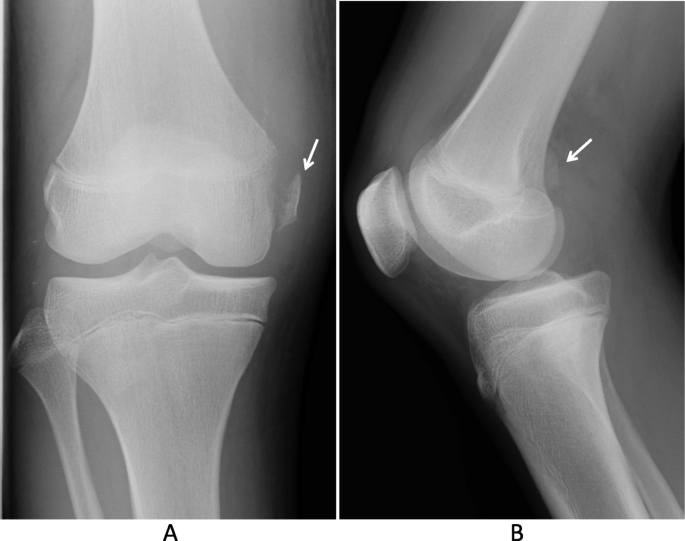

Most avulsion fractures are treated conservatively with pain and swelling control and early return to activities. However, if the fracture is. Clinical and radiographic findings confirmed the presence of an avulsion fracture at the proximal attachment of the mcl, combined with complete anterior cruciate ligament (acl) and posterior cruciate ligament (pcl) rupture.